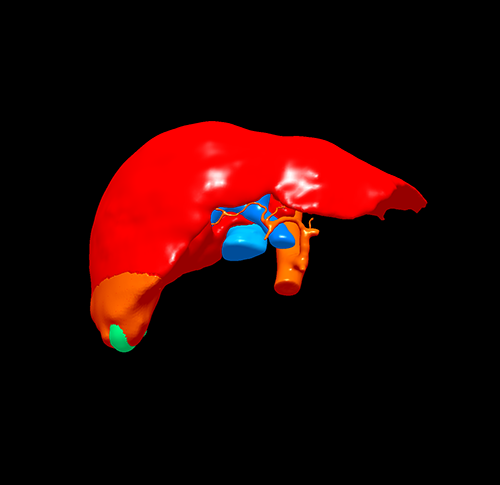

三维重建

S6肝癌--腹腔镜S6部分切除